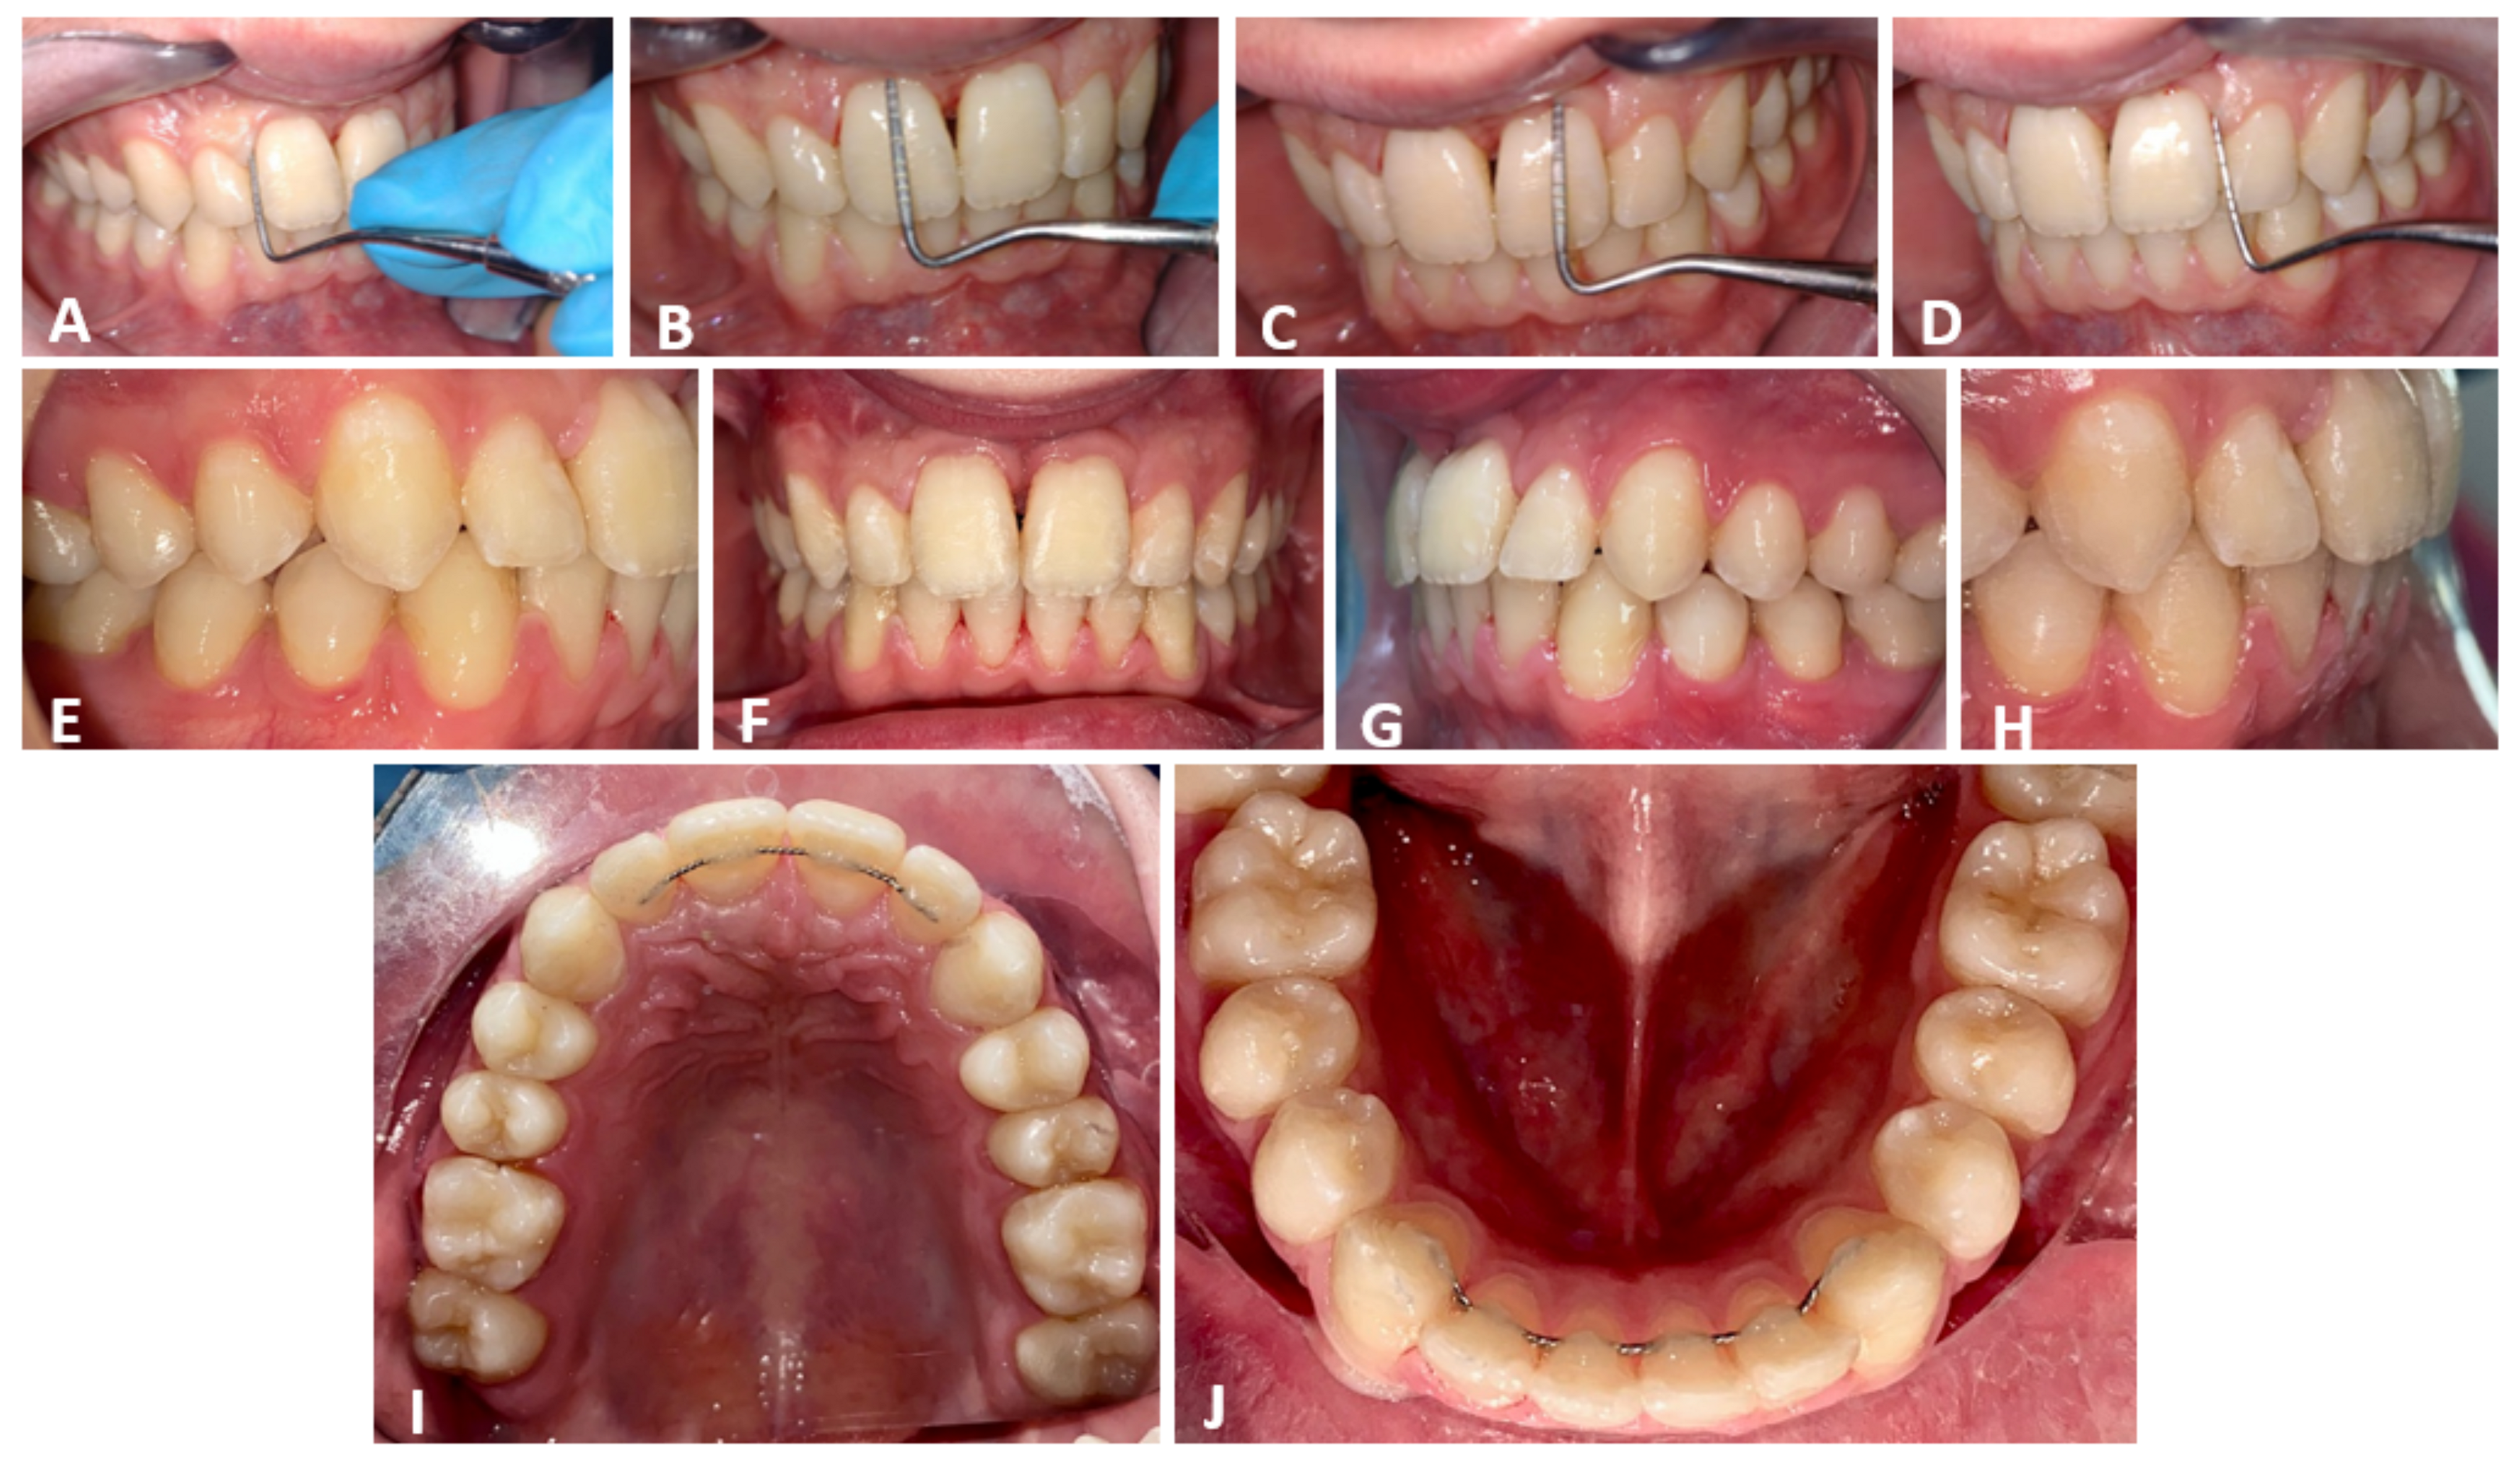

2.2. Clinical Exams and Diagnosis

2.3. Therapeutic Plan

3. Results